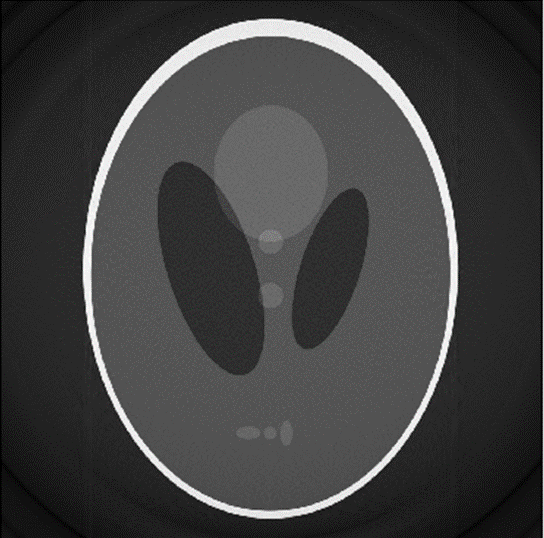

Applying this filter to the sinogram as seen in Figure 4: sinogram of shepp-logan phantom, creates the sinogram in Figure 7 and reconstructing of this sinogram can be seen in Figure 34.

Figure 8: reconstruction from the sinogram in figure 8

The reconstructed image is sharper with more of the finer details showing through. Although within the image there still is some noise as well as a lack of contrast. The reconstruction also has the same circle around it as the non-filtered reconstruction.

Comparing the reconstructions of the images as seen in Figure 5 and Figure 8, the filtered back projection creates a clearer image than the non-filter one. The reasoning for this almost bloom effect on the non-filtered image is the polar sampling in the Fourier slice theorem. This polar sampling causes the bloom effect as there are more samples near the center in Fourier space. These samples near the center correspond to low frequencies, so during the back filtering more lower frequencies samples are captured. This difference in the number of low frequencies captured compared to high frequencies causes most of the details in the image to be lost. These details get lost as these details tend to reside mostly within the higher frequencies in Fourier space. The filter image also shows a noise within the image. This is because the filter that was used is a ramp filter. This type of filter disproportionally amplifies the higher frequency in Fourier space. Although in this case where the higher frequency were the ones that were sample less, the effect is less noticeable. However, this noise could be reduced by using a higher order filter rather than this basic ramp filter. There are also circles that appear around both filtered and non-filtered reconstruction. These circles are more than likely to come from the forward projection stage when the image matrix is rotated. This would occur as during this stage the forward projected image is resampled as well as receiving some interpolation.